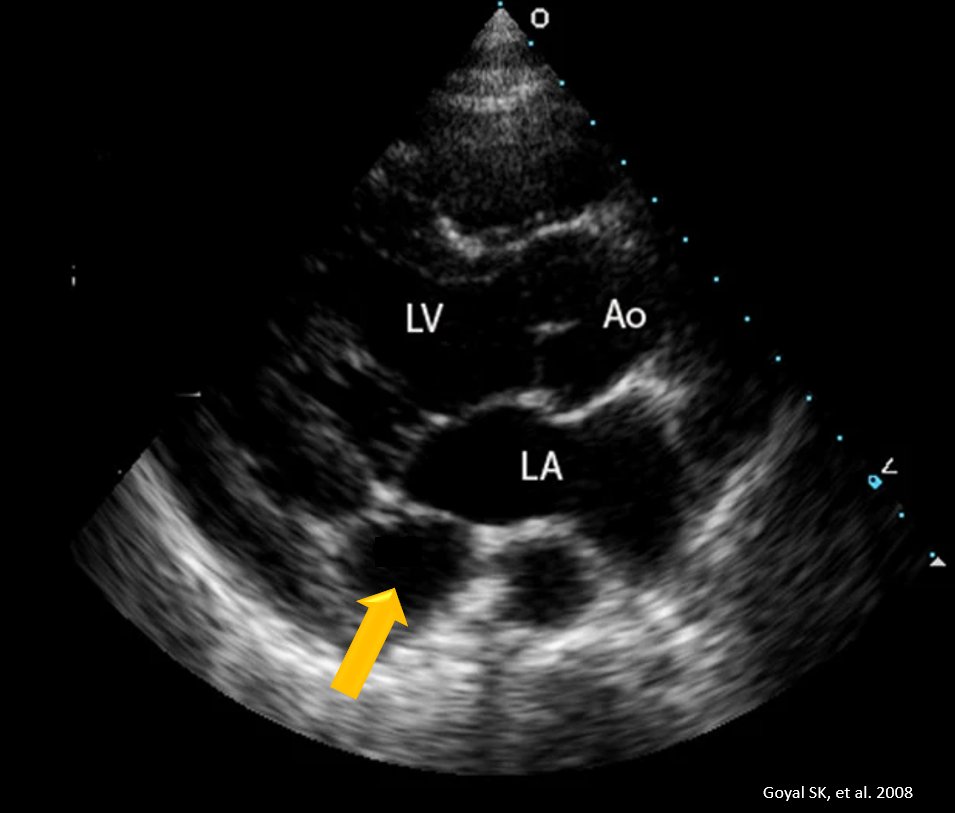

Коронарная фистула мкб 138 фото